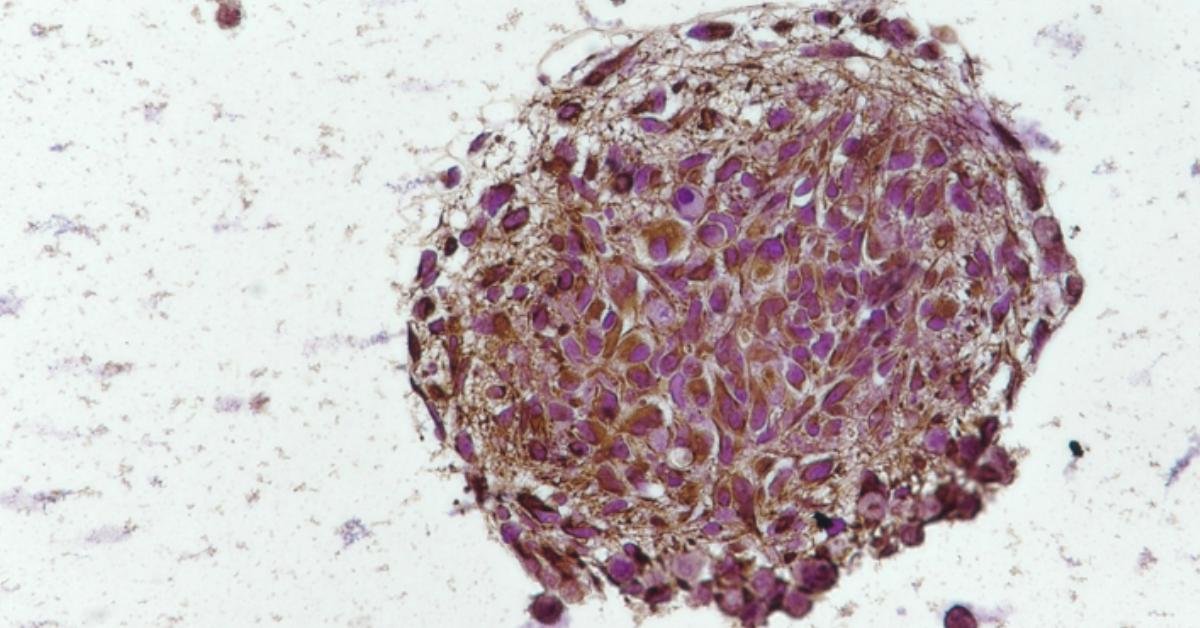

(IN BRIEF) A review published in Nature Reviews Neurology highlights how researchers at the Luxembourg Institute of Health, in collaboration with the University of Luxembourg, are advancing brain tumour research through the development of organoid models. These three-dimensional, patient-derived structures replicate the complexity and diversity of real tumours more accurately than traditional laboratory methods, enabling improved study of tumour behaviour, progression, and treatment resistance. The research also underscores the growing importance of combining organoids with genomic and molecular profiling to better understand cancer drivers. In addition to supporting fundamental research, organoids offer significant potential for drug screening, allowing scientists to test therapies on patient-specific tumour models and identify more effective treatment strategies. While challenges remain, organoids are increasingly viewed as a key link between laboratory discoveries and clinical applications, paving the way for more personalised approaches to treating brain tumours.

Brain tumours remain among the most challenging cancers to investigate due to their highly diverse and constantly evolving nature. They consist of complex populations of tumour cells that interact dynamically with their surrounding microenvironment. Conventional research models, particularly two-dimensional cell cultures, often fail to capture this level of complexity, limiting their effectiveness in understanding tumour biology and predicting treatment outcomes.

Organoids provide a promising alternative. These three-dimensional structures, developed from patient-derived tumour samples, are capable of preserving many of the defining features of the original tumour, including its cellular diversity and spatial organisation. This allows researchers to study tumour initiation, progression, and resistance to therapies in a setting that more closely reflects real conditions. In addition, scientists are increasingly combining organoid models with genomic and molecular analyses to better identify the mechanisms driving tumour behaviour.

In the review, researchers from the Luxembourg Institute of Health and the University of Luxembourg outline recent advancements in organoid technology and its potential to transform the study and treatment of complex brain cancers. These models enable the preservation or recreation of key tumour characteristics, offering researchers a controlled environment to observe how tumours evolve and respond to different therapeutic approaches.

Anna Golebiewska, lead author of the study and head of the NORLUX Neuro-Oncology laboratory at LIH, emphasizes that organoid models make it possible to retain the complexity of a patient’s tumour while enabling detailed experimental investigation. This provides valuable insight into disease progression and treatment response.

Beyond their role in basic research, organoids are increasingly being explored as platforms for functional drug screening. By testing various treatments on patient-derived organoids, researchers can potentially identify the most effective therapies before they are applied in clinical practice, supporting more personalised treatment strategies.

Although technical and logistical challenges still need to be addressed, organoid technologies are expected to play an important role in bridging laboratory research and clinical care. As these models continue to evolve, they are likely to become central to delivering personalised solutions for patients with aggressive and complex brain tumours.